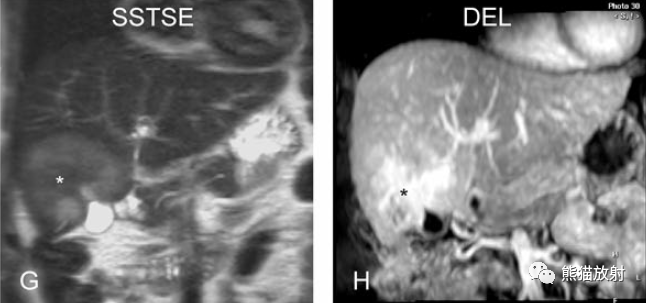

膽囊癌。病灶以膽囊為中心侵及肝臟,明顯彌散受限,由于病灶內(nèi)含結(jié)締組織/纖維成分(T2低信號(hào))導(dǎo)致肝被膜內(nèi)陷,增強(qiáng)掃描動(dòng)脈期明顯不均質(zhì)強(qiáng)化,延遲期中心纖維成分延遲強(qiáng)化。表現(xiàn)類(lèi)似肝內(nèi)膽管細(xì)胞癌。